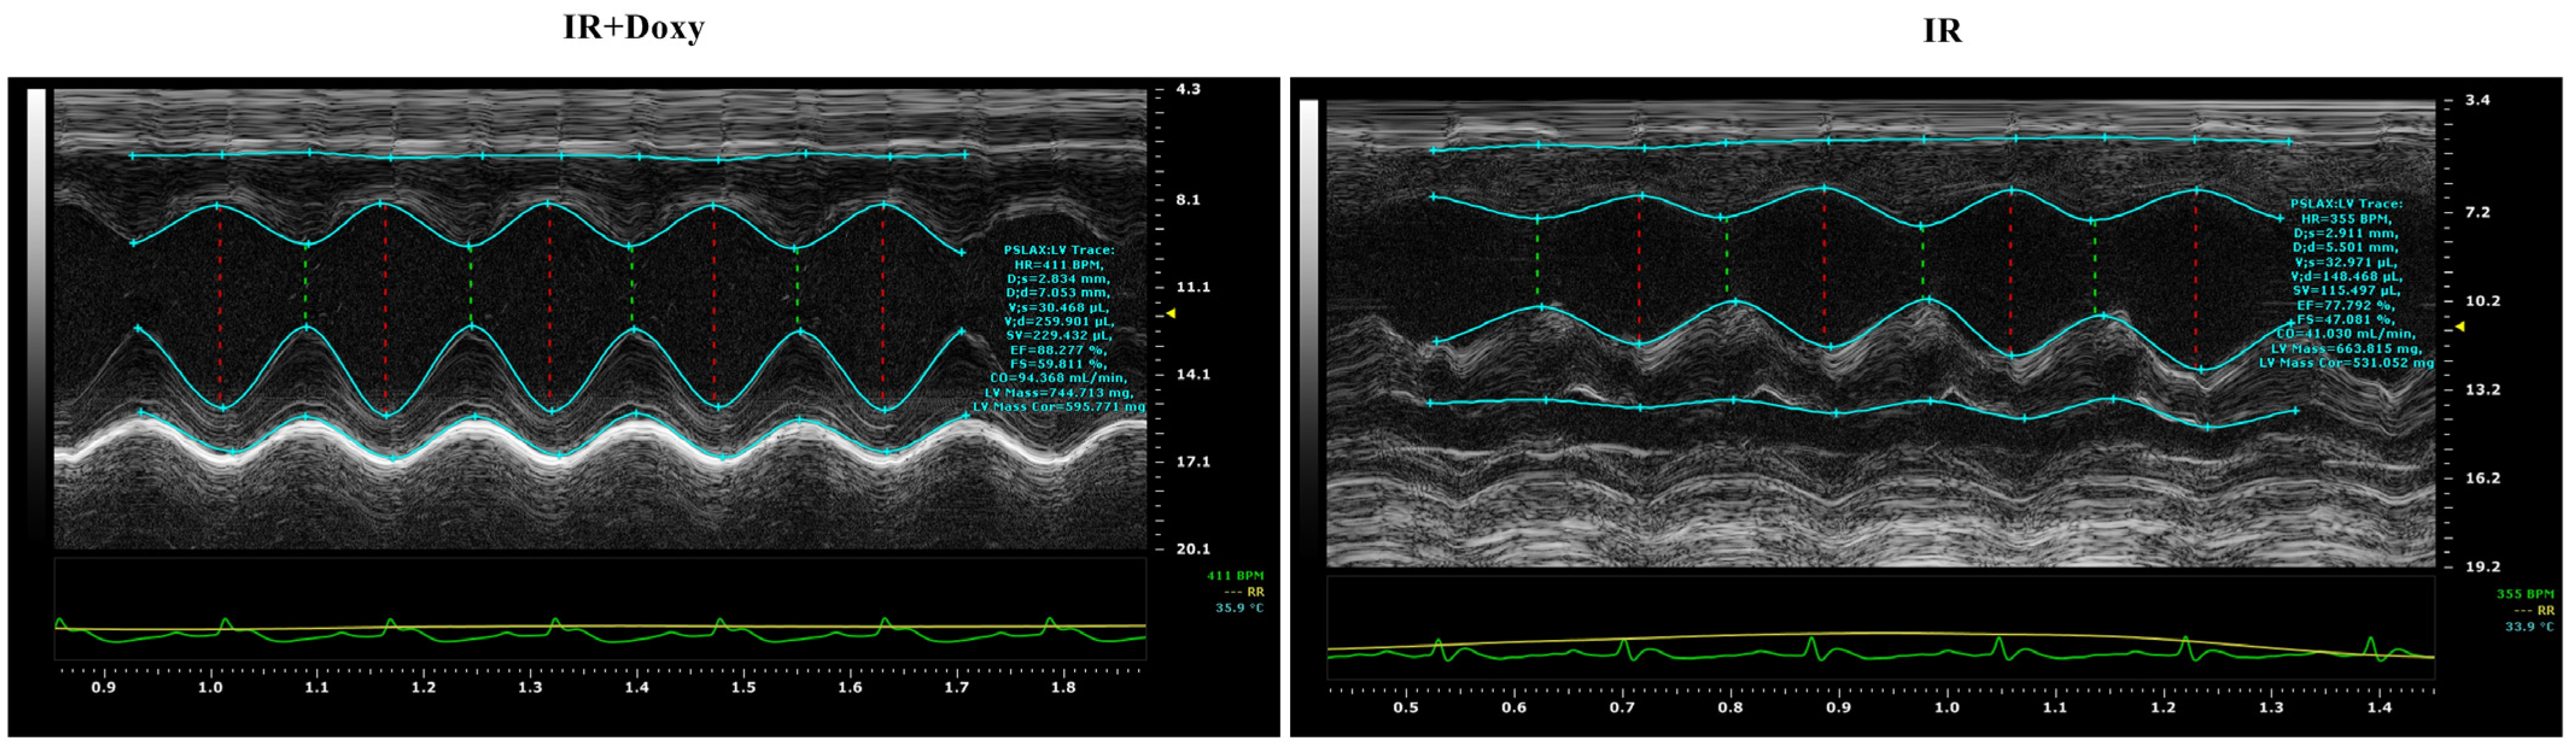

3.3. Doxycycline Protects from I/R Associated Impairment of Left Ventricular Function

| Echocardiographic Parameters | Heart Rate (bpm) | Cardiac Output (mL/min) | Stroke Volume (µL) | Fractional Shortening (%) | Ejection Fraction (%) | Enddiastolic Volume (µL) | Endsystolic Volume (µL) | |

|---|---|---|---|---|---|---|---|---|

| baseline | sham | 386.7 ± 20.2 | 64.7 ± 12 | 206 ± 27.4 | 48.2 ± 5.7 | 87.1 ± 2.5 | 176.6 ± 36 | 36.77 ± 8 |

| I/R | 349.3 ± 30.3 | 68 ± 12 | 204.4 ± 21.6 | 46.2 ± 10.9 | 79.4 ± 11.5 | 159.8 ± 46.7 | 26.77 ± 12.6 | |

| I/R Doxy | 384.2 ± 48.6 | 83.6 ± 31 | 211.1 ± 55.4 | 51.32 ± 3.7 | 83.3 ± 11.8 | 174.9 ± 42.3 | 32.49 ± 17.6 | |

| 7 days | sham | 408.7 ± 16.3 | 80.9 ± 9.7 | 212.5 ± 30 | 48.53 ± 5.5 | 95.11 ± 5.7 | 176.5 ± 17 | 38 ± 5.6 |

| I/R | 378.3 ± 35 | 51.73 ± 15.6 | 140 ± 25.1 | 27.56 ± 7.5 | 63.59 ± 12.9 | 290 ± 99.8 | 60.93 ± 13.77 | |

| I/R Doxy | 384.4 ± 23 | 89.24 ± 18.4 | 201.4 ± 45.2 | 49.02 ± 12.9 | 87.69 ± 6 | 219 ± 54.4 | 26.03 ± 9.8 | |

| 14 days | sham | 369.3 ±18 | 87.18 ± 17.5 | 220.9 ± 29.3 | 50.64 ± 2 | 93.21 ± 2 | 184.7 ± 15 | 28.78 ±7.7 |

| I/R | 378 ± 34.9 | 54.71 ± 13.1 | 111.6 ± 44 | 35.06 ± 8.8 | 64.99 ± 12.2 | 280.3 ± 78 | 55.7, ± 32.9 | |

| I/R Doxy | 391.2 ± 43.5 | 79.17 ± 11.4 | 194.6 ± 36.3 | 50.51 ± 7.6 | 86.38 ± 5 | 219.4 ± 54 | 31.93 ±11.5 | |

| p | sham vs. I/R | 0.328/0.313/>0.99 | 0.971/0.049 */0.009 * | 0.996/0.032 */0.006 * | 0.934/0.018 */0.012 * | 0.57/0.002 */0.002 * | 0.844/0.006 */0.016 * | 0.566/0.033 */0.002 * |

| sham vs. I/R Doxy | 0.995/0.502/0.201 | 0.446/0.756/0.49 | 0.983/0.9/0.636 | 0.864/0.997/0.1 | 0.882/0.582/0.573 | 0.999/0.39/0.827 | 0.907/0.36/0.924 | |

| I/R vs. I/R Doxy | 0.266/0.931/0.791 | 0.427/0.004 */0.037 * | 0.947/0.033 */0.012 * | 0.556/0.005 */0.004 * | 0.812/0.004 */0.004 * | 0.826/0.037 */0.020 * | 0.767/0.001 */0.001 * | |